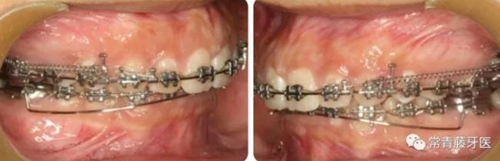

治療過程

A67、B67之間植入微種植釘整體內(nèi)收上牙列,下頜配合多用途弓整平牙列改善覆合。

繼續(xù)內(nèi)收上牙列,此時下頜spee曲線基本整平。